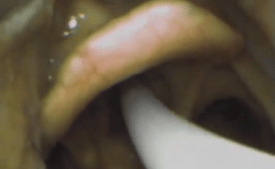

For the Laryngeal Mask Airway the insertion technique is similar to placing an Oropharyngeal Airway. Slide device with steady pressure into the mouth towards the floor then round the back of the tongue with pressure towards your hips. You may feel a distinctive ‘pop’.

After successful insertion remember to inflate the device before attempting to ventilate (you often see and feel a ‘pop)’. Some advanced devices have a port for a Nasogastric tube.